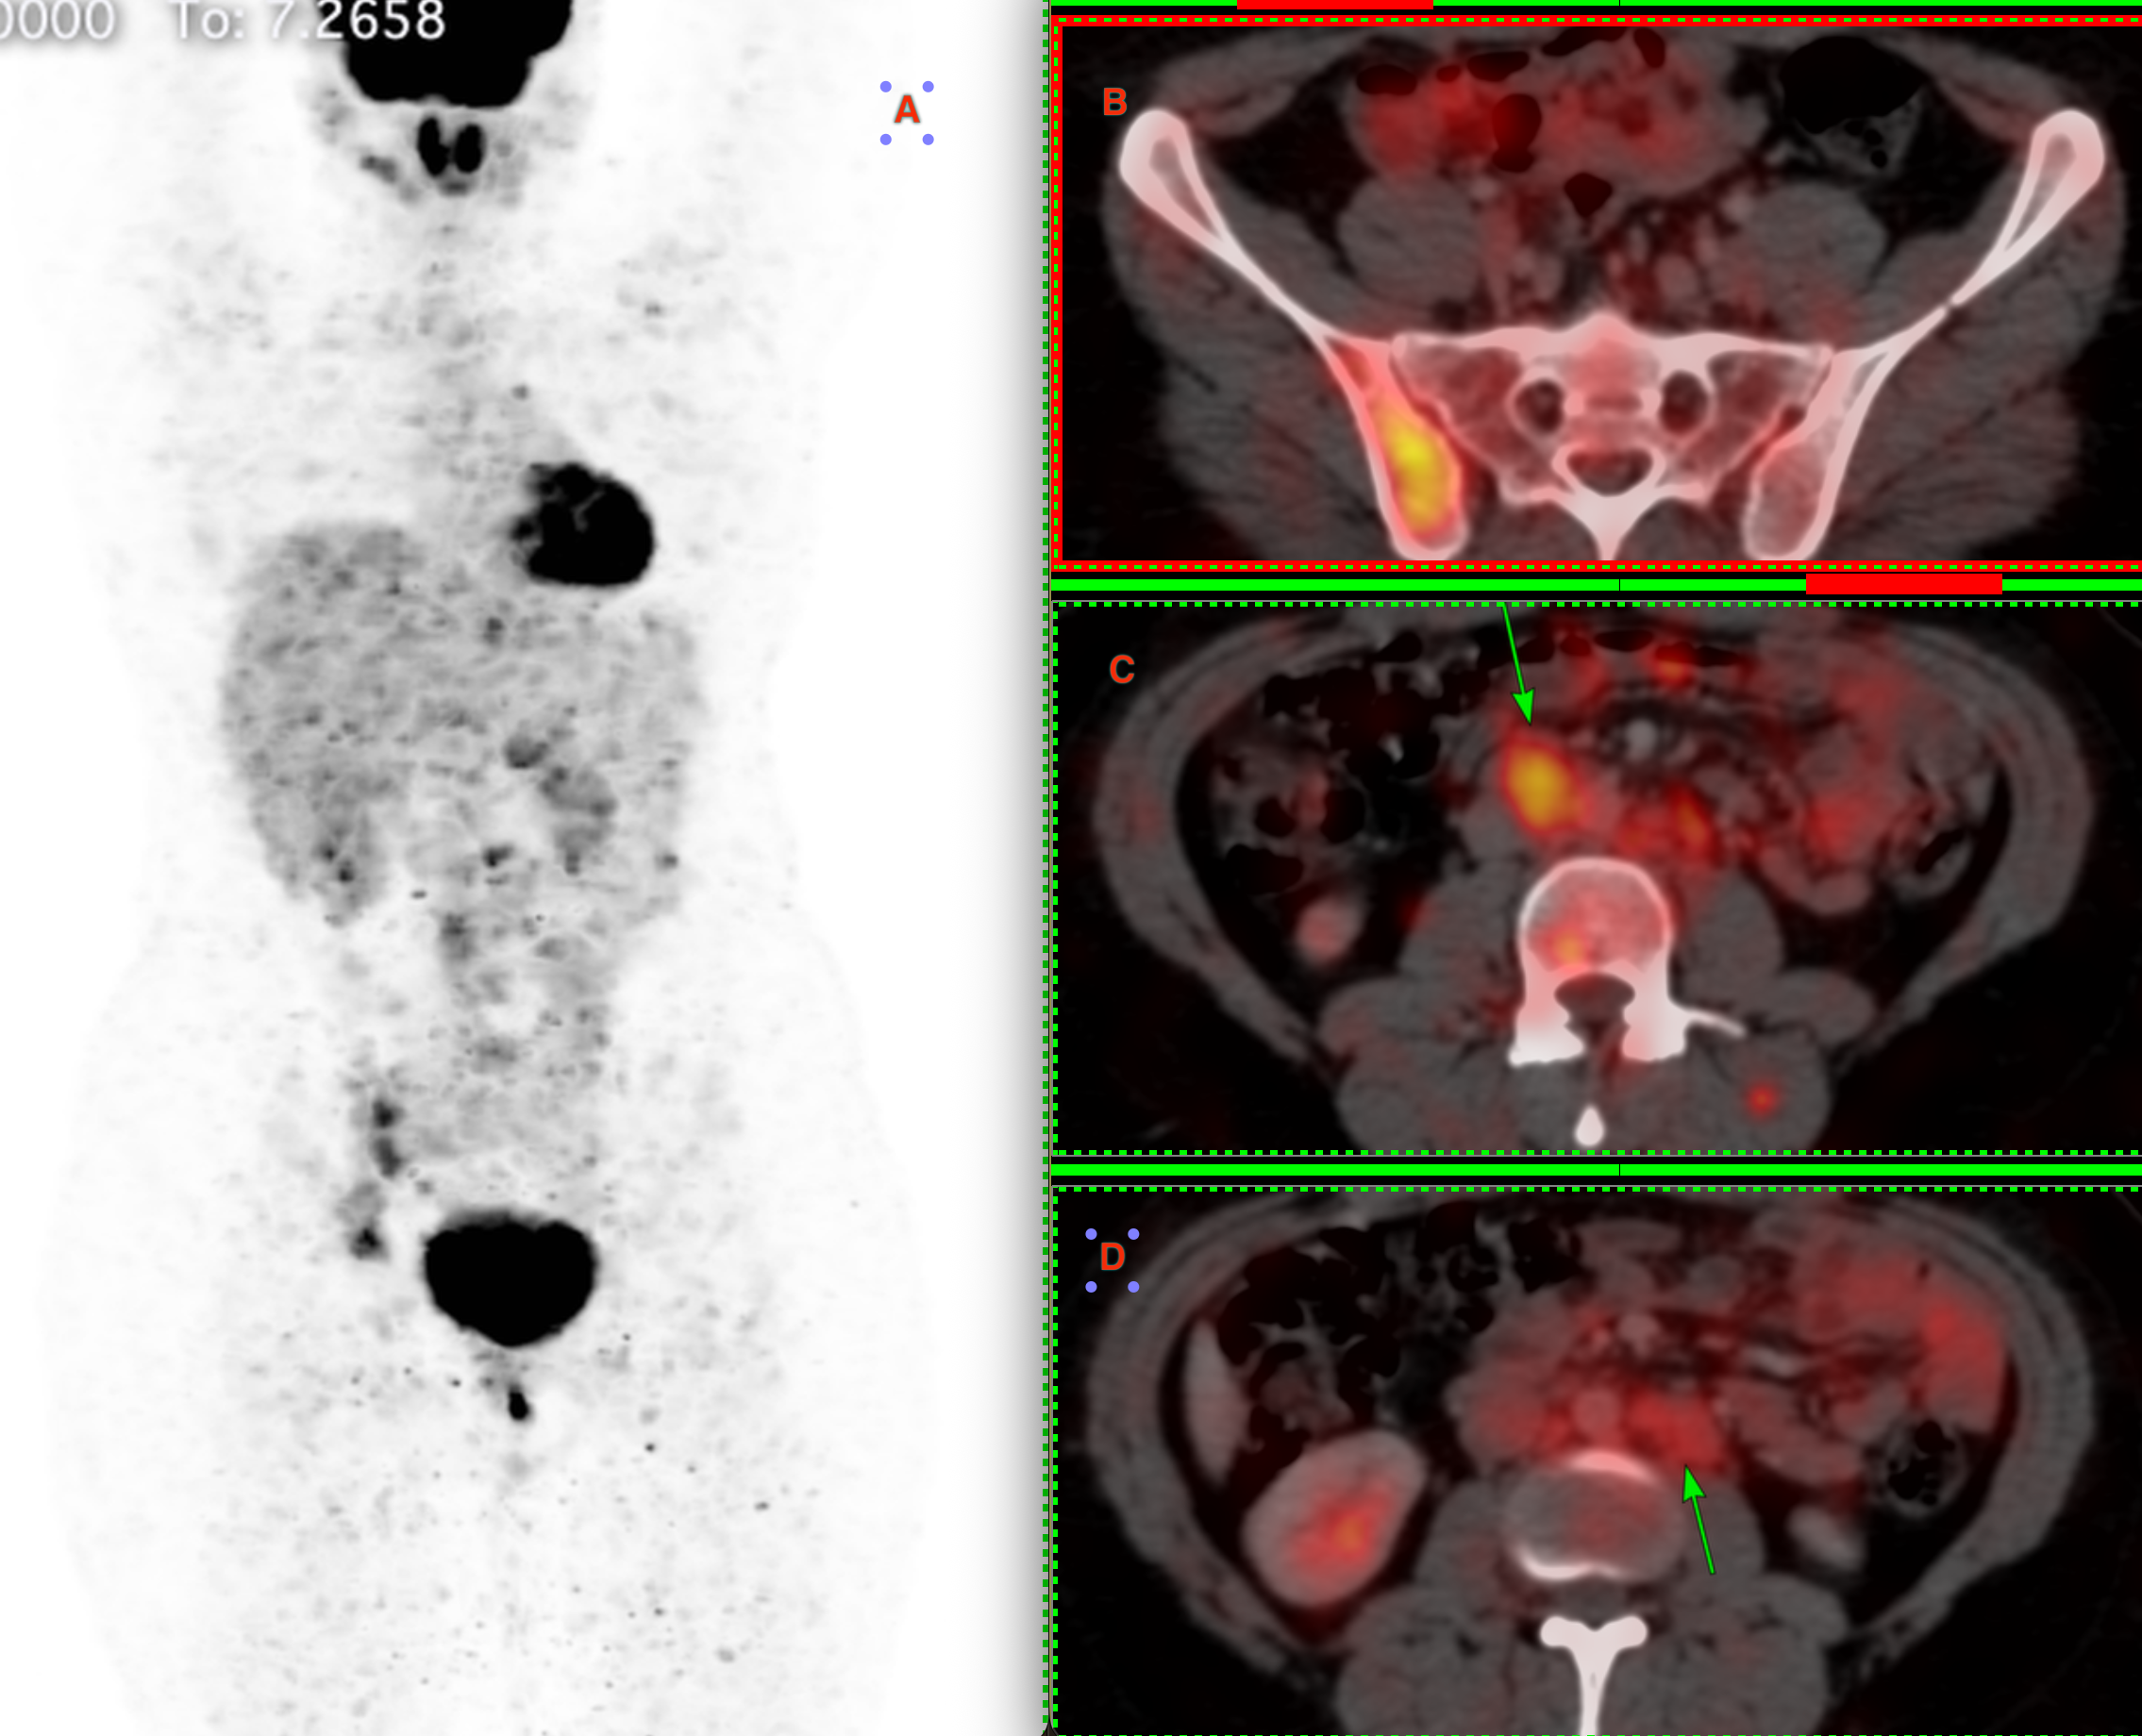

22-years old treated 5 years ago for dysgerminoma had back back and MRI showed a right iliac bone lesion. PET-CT (Fig. 1) showed uptake in the lesion (A) but also aortocaval (C) and retroperitoneal para-aortic nodes.

The aortocaval node had the most activity and the onco team asked for a biopsy of this node.